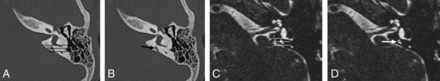

The second group with both CT and MR imaging available included 41 patients and 81 ears with an age range of 0.3–15 years (mean, 10.8 years; male/female ratio = 1.3:1). The midaperture width of 81 ears with diagnostic imaging of the temporal bone on both HRCT and MR imaging was measured (a single patient had diagnostic imaging of only 1 ear). VA size on CT ranged from 0 to 0.8 mm (mean, 0.51 mm; 95% measuring ≤0.8 mm). In this same group, the ELD midaperture width measured by MR imaging ranged from 0 to 0.8 mm (mean, 0.36; 95% measuring ≤0.8 mm). A significant correlation was present between measurements on HRCT and MR imaging, with a Spearman correlation of 0.65 (P < .001) (Fig 2). Agreement between the modalities was moderate, with an intraclass coefficient of 0.618 (95% CI, 0.463–0.736). Overall, MR imaging tends to have smaller midaperture ELD widths compared with the VA on HRCT (Fig 3). Many small VAs on HRCT (normal-sized) were not visualized on MR imaging (Fig 4).

Scatterplot comparing midaperture measurements on CT and MR imaging.